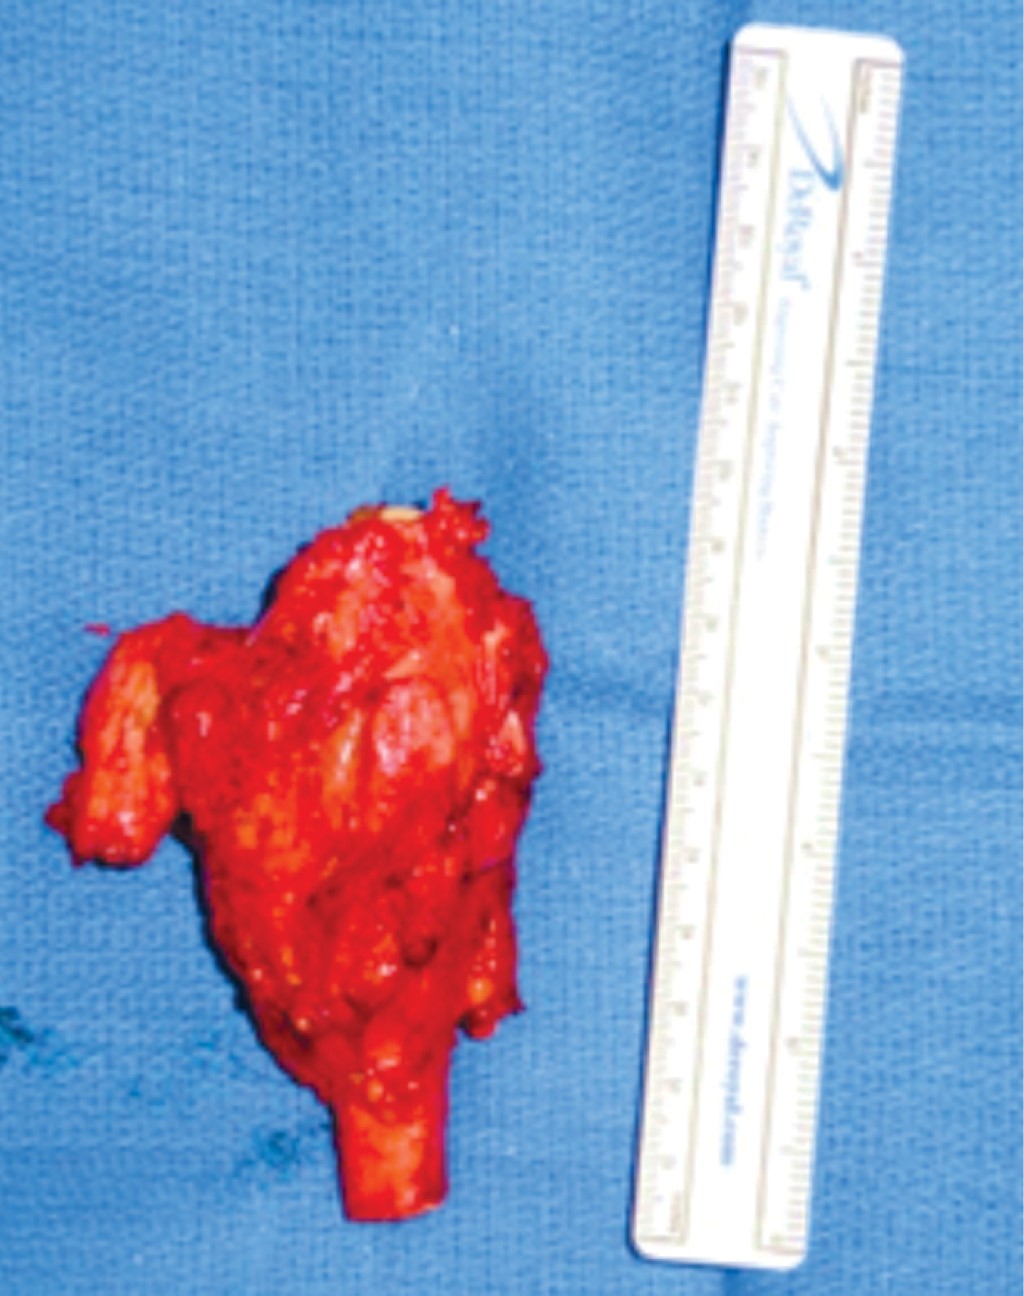

Presentamos el caso de una mujer de 45 años, sin antecedentes crónico degenerativos de importancia, que acude por presentar dolor en muñeca izquierda, con el antecedente de una fractura patológica de radio distal izquierdo en septiembre de 2018, tratada con reducción abierta y fijación interna con placa de radio distal volar y matriz ósea, actualmente consolidada. De inicio se realizó radiografía posteroanterior y lateral de la muñeca observando una lesión neoplásica en radio distal compatible con un tumor de células gigantes en un estadio III de la clasificación de Campanacci (Figura 1), se complementó el protocolo de estudio con tomografía de tórax descartando metástasis pulmonares y posteriormente se decidió como tratamiento la resección en bloque (Figura 2) (5 cm a la superficie articular proximal tanto de radio como de cúbito y se incluyó la fila proximal del carpo, todo a través de un abordaje dorsal) y reconstrucción inmediata con peroné vascularizado y artrodesis de muñeca con una placa de compresión bloqueada (Figura 3).